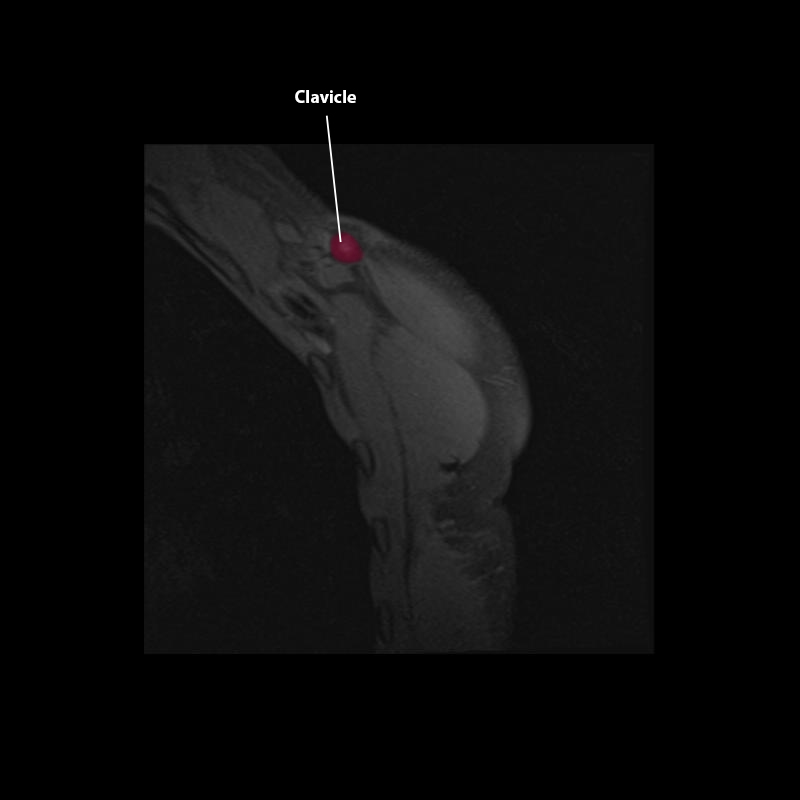

Shoulder MRI Anatomy